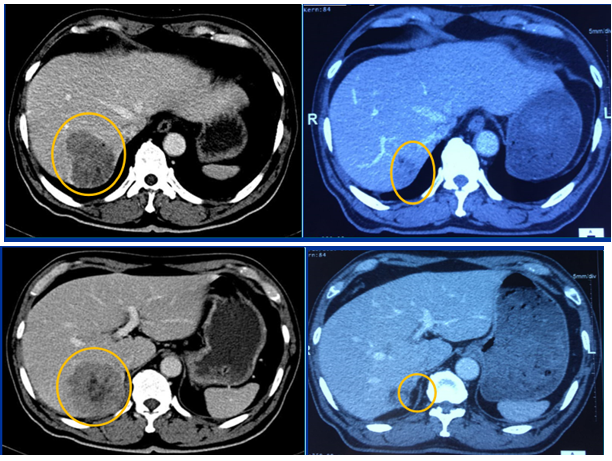

• Hình ảnh Cắt lớp vi tính ổ bụng

Hình 1: Nhu mô gan hạ phân thùy V có khối kích thước 48x51mm tính chất của HCC (ung thư biểu mô tế bào gan) (mũi tên xanh). Tĩnh mạch cửa không thấy huyết khối.

Hình ảnh cắt lớp vi tính ổ bụng sau 3 tháng:

Hình 3: Bên trái: trước điều trị u gan hạ phân thùy V kích thước 48x51mm. Bên phải: sau điều trị 3 tháng u gan giảm kích thước 22x25mm